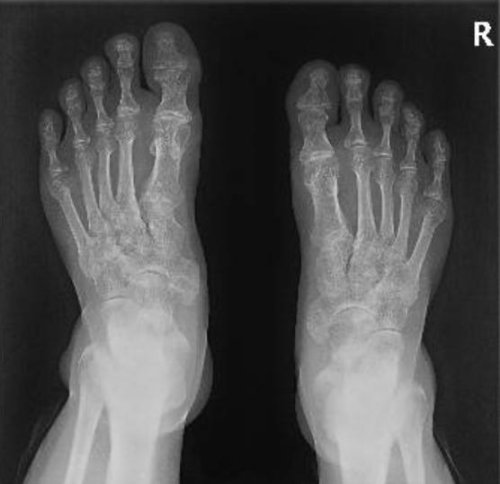

李伯双足X线片见双侧脚趾多处小囊状骨质破坏。通讯员供图

为了进一步明确病因,科室为李伯进行了多项检查,结果显示,李伯类风湿关节炎的特异性抗体均阴性,双足X线片见双侧脚趾多处小囊状骨质破坏。随后,科室为李伯进行了右肘关节结节活检术,术中取出完整痛风石。果然,困扰了李伯多年的罪魁祸首就是痛风!